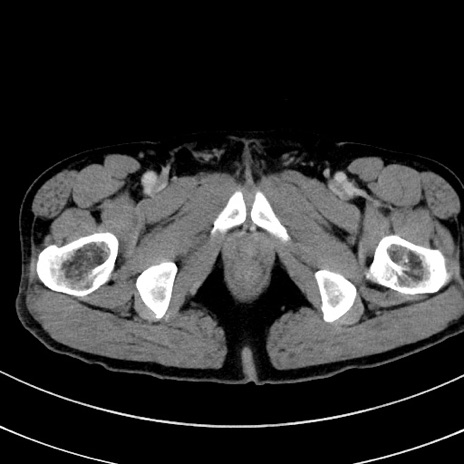

症例8(横断像)

【症例】 60歳代男性

【主訴】 黒色吐物

【現病歴】 4日前から嘔気自覚、2日前の朝食後にも嘔気あり、自分で手で嘔吐反射起こし嘔吐したところ血が混ざっていたため受診。

【既往歴】 5年前汎発性腹膜炎を伴う急性虫垂炎で手術、高血圧、前立腺肥大症、高脂血症

【身体所見】 腹部正中に手術癩痕あり 腹部平坦・軟圧痛なし膨満感あり

【データ】WBC 8400、CRP 4.54